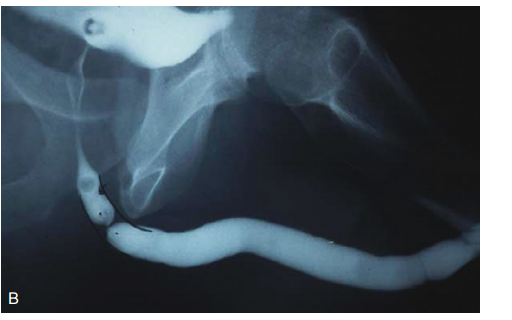

• Уретрографія – рентгенологічне дослідження з контрастом.